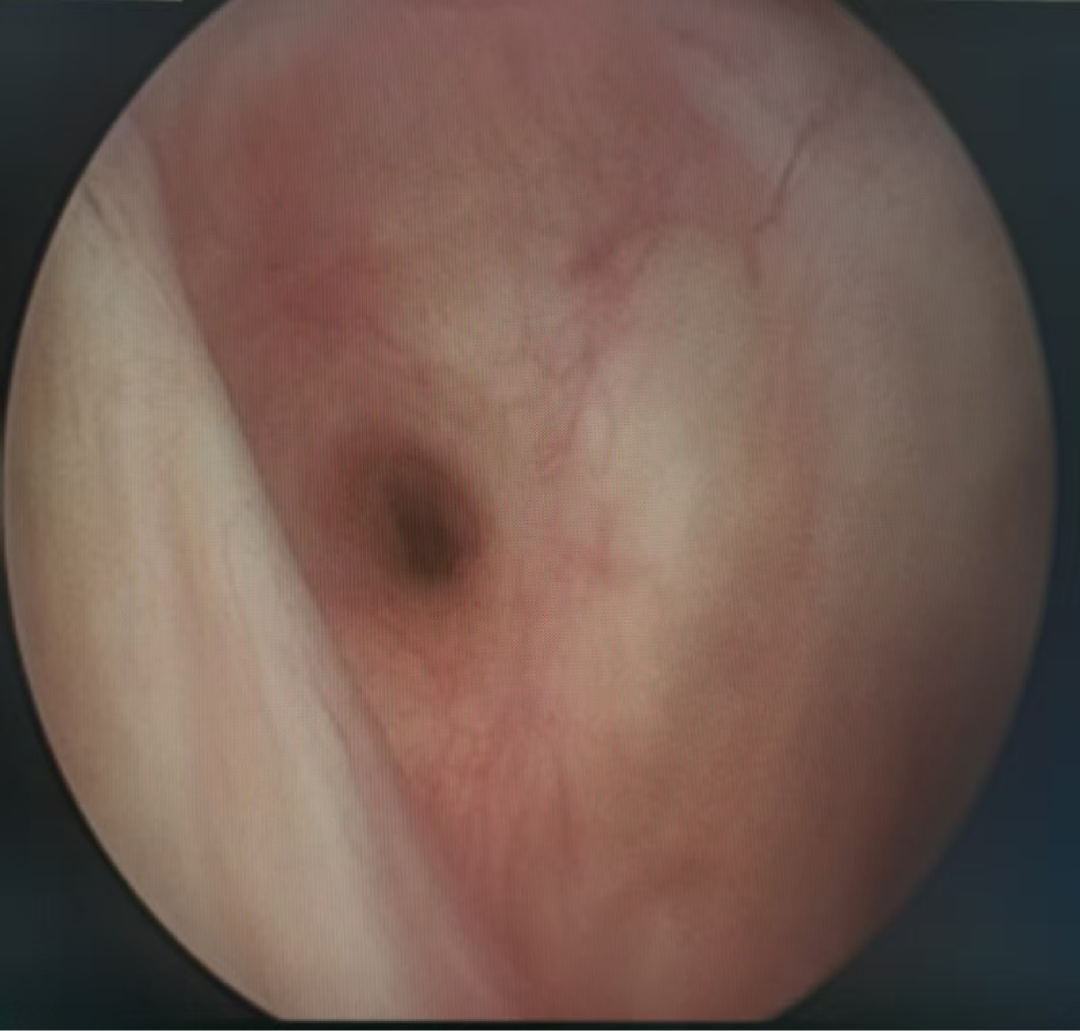

肿瘤不仅侵犯膀胱肌层,更累及了右侧输尿管壁内段。传统的处理方式是行膀胱根治性切除术。但患者保膀胱意愿强烈,MRI检查提示为局限性MIBC,试行经尿道保膀胱手术。

术后半年复查,无肿瘤复发转移,右侧输尿管开口形态良好,喷尿正常。可见,通过经尿道的精准器械组合,我们帮助局限性MIBC患者实现了“保卫膀胱”的目标